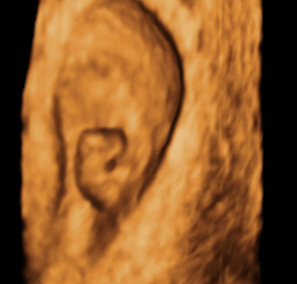

Se esboza la cara de un bebé con 7 semanas

Los rasgos de su cara siguen sin definirse, aunque aparecen unos diminutos ojos. Al final de esta semana, en la cara surgen unos brotes: una pequeña fosa que será la boca, los brotes de los maxilares inferior y superior y unas diminutas aberturas que señalan dónde se situará la nariz. También aparecen los esbozos de las orejas.